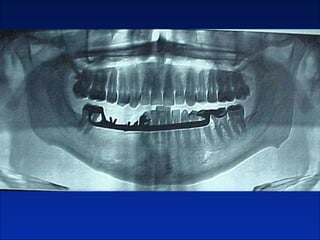

Queratoquiste odontogenico

Reseccion quirurgica de queratoquiste odontogenico

Cuatro años después

Otro caso